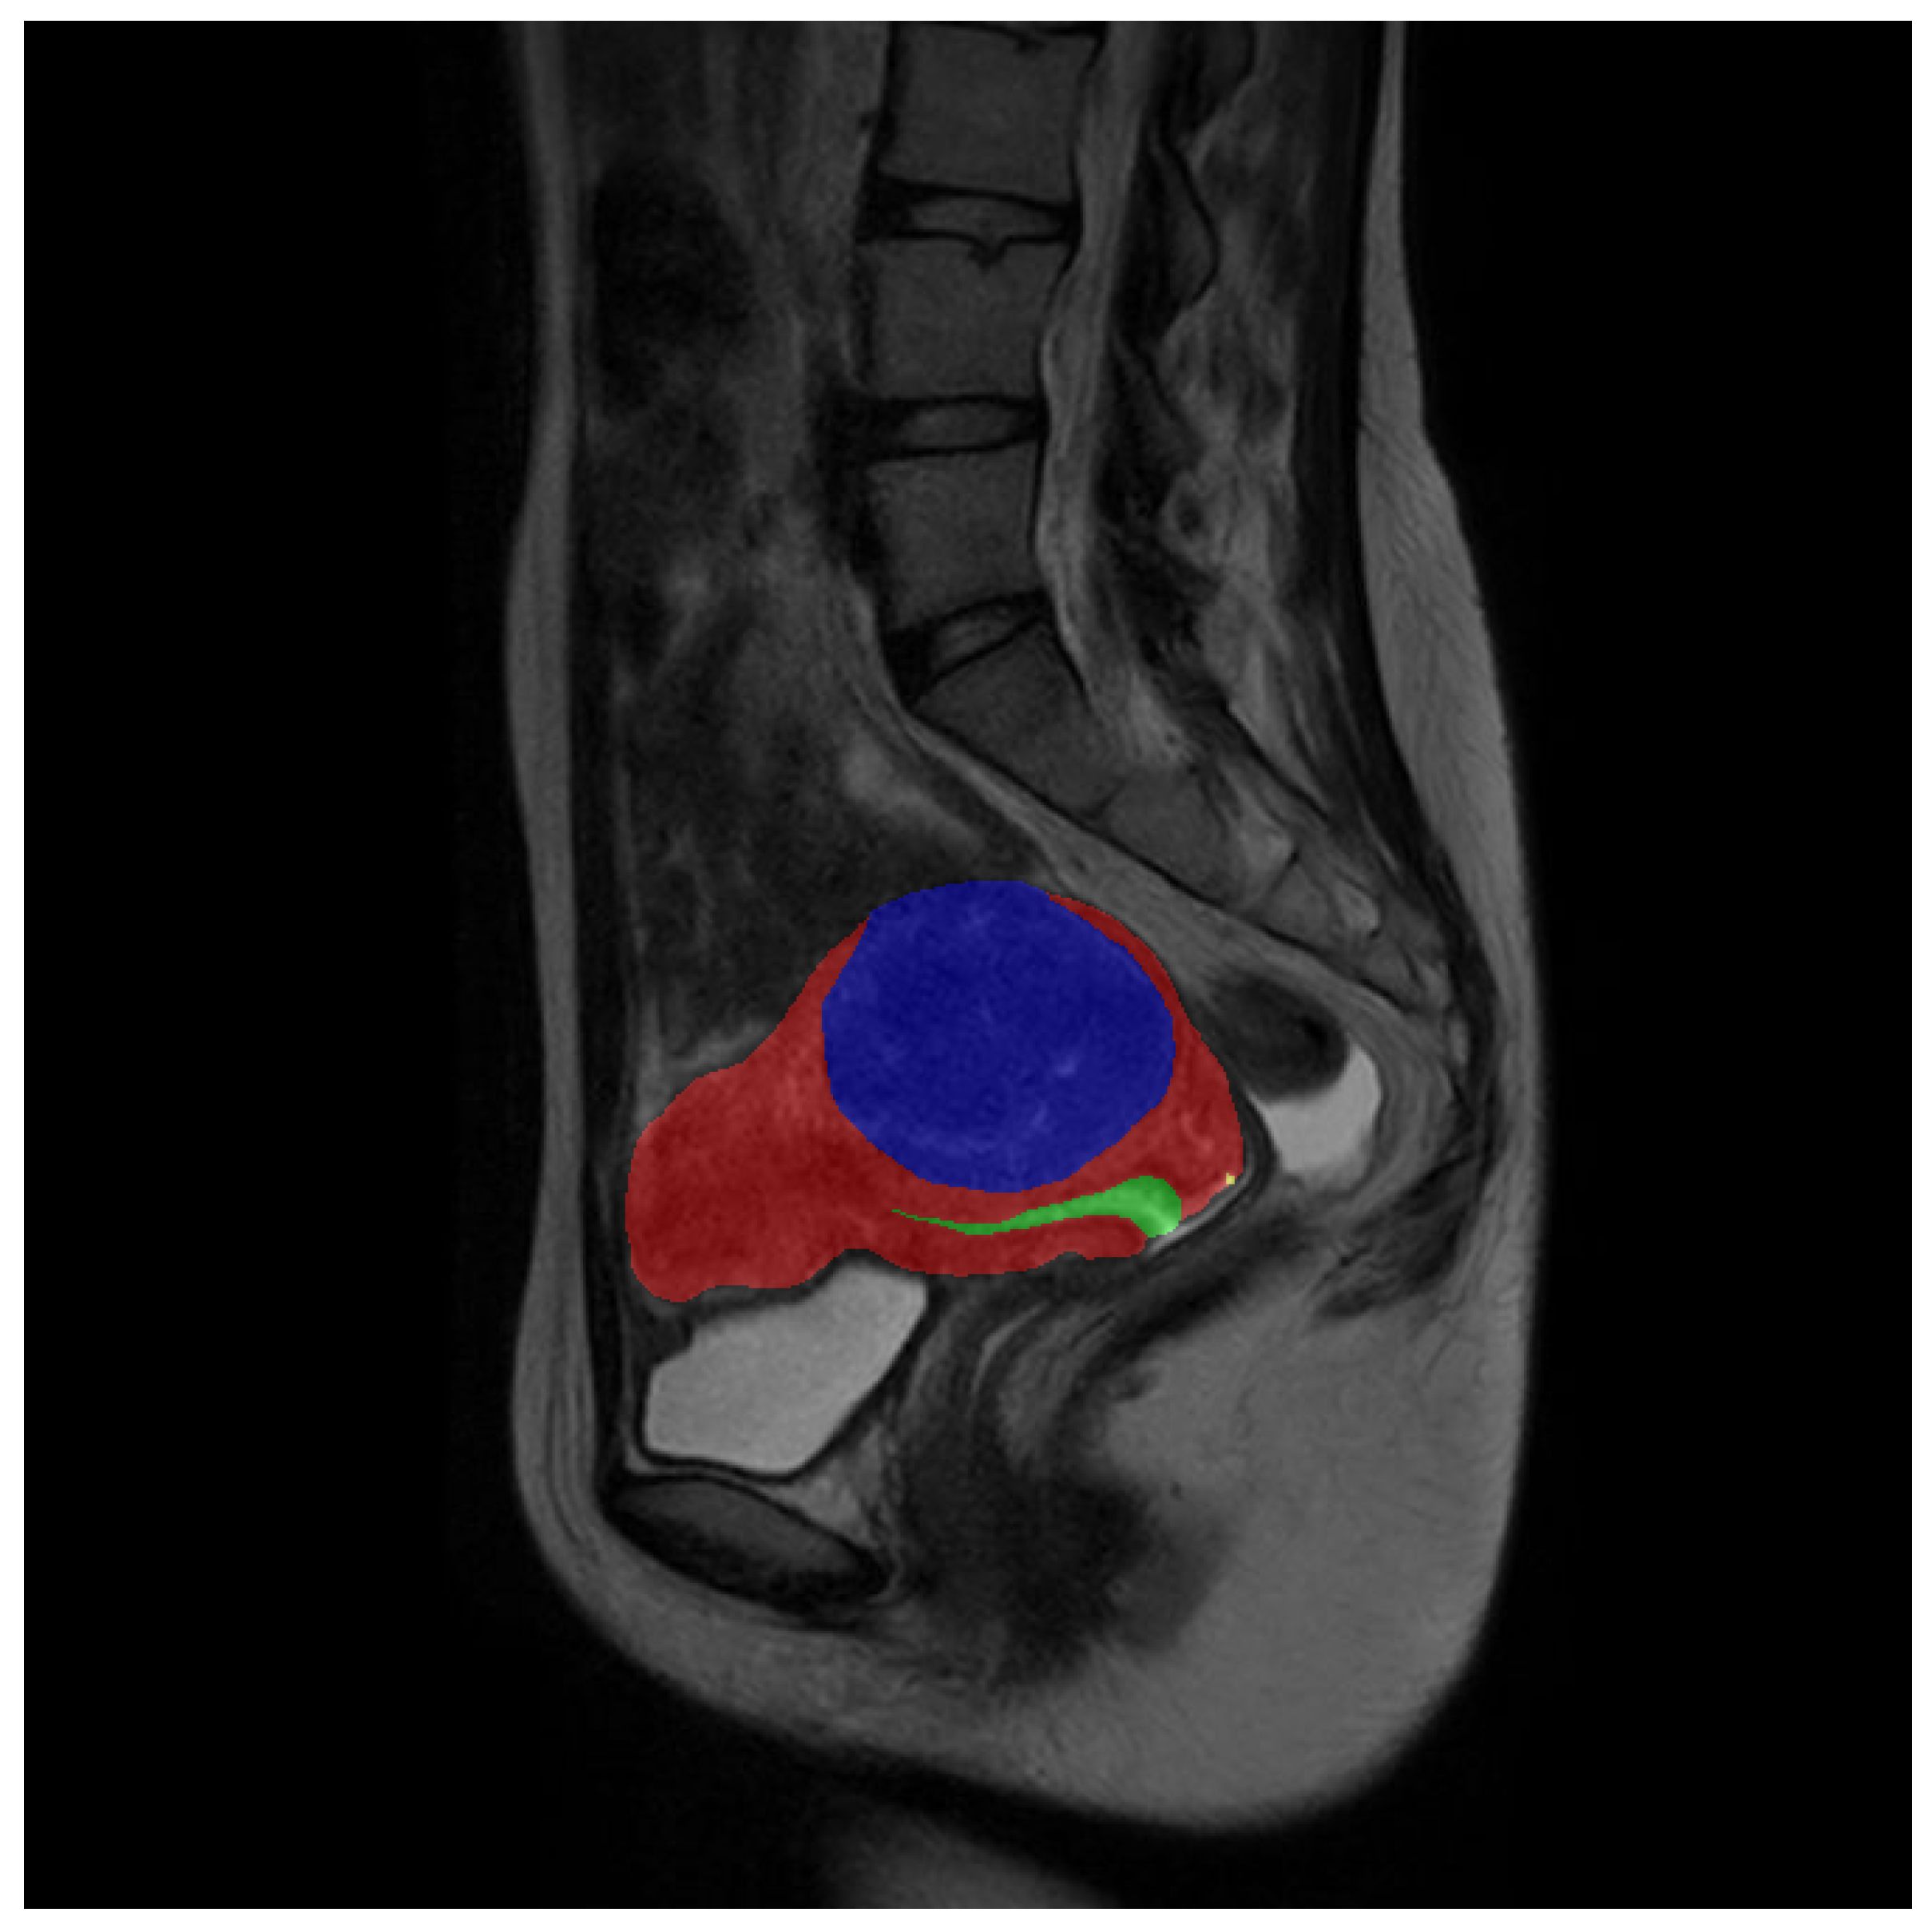

To provide a clearer visualization of the improvement in the segmentation effect of the low-frequency class achieved by our model, we conducted visualization processing on the experimental reasoning results. The visualized results are presented in Figure 7 and Figure 8.

Figure 7 mainly reflects the overall predicted situation and describes the difference between the precision and sensitivity ratio of the predicted results, and Figure 8 shows the improvement of the model in the low-frequency class (nabothian cyst).

Figure 8. Comparison of visual inference results—nabothian cyst: The three columns of the images show the predicted values of the expected baseline and the predicted values of our proposed model, respectively. During visualization, the uterine wall was covered in red, the uterine cavity was covered in green, myomas of the uterus were covered in blue, and nabothian cysts were covered in yellow.